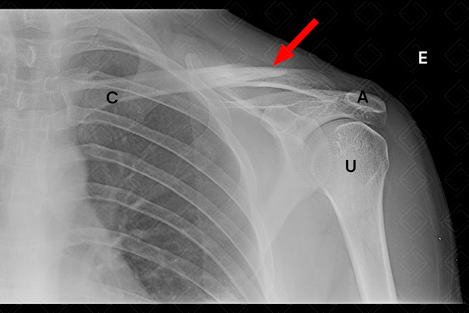

Texto alternativo para a imagem Legenda das siglas: A = acrômio da escápula; C = clavícula; U = úmero. Créditos: Athena Hub/Medical Harbour

Descrição da figura: Radiografia de clavícula esquerda AP evidenciando traço de fratura, com desalinhamento no seu terço médio (seta vermelha). [cms-watermark]